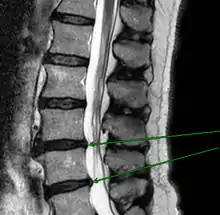

Попере́кові хребці́ (лат. vertebrae lumbales) — п'ять нижніх хребців у людини з 20-го по 24-й, рахуючи зверху. Поперековий відділ хребта з'єднується нижче з крижами (нижній поперековий хребець L5 з'єднується з верхнім крижовим хребцем S1), вище — з грудним відділом хребта (L1 з'єднується з нижнім грудним хребцем Th12).

Механічний зсув одного з поперекових хребців, переохолодження, локальна інфекція, пухлини, деградація тканин, можуть привести до запального процесу в хребетно-руховому сегменті, з наступними мучительними болями, вимушених положень тіла. Дуже поширеною причиною патології в поперековому відділі хребта є неправильний розподіл навантаження на поперековий відділ хребта, коли додаткова вага (а іноді і власна вага) підіймається з лише одним важелем в поперековому відділі хребта. Частим захворюванням в поперековому відділі хребта є грижі міжхребцевих дисків — випинання пульпозного ядра диска за межі його фіброзного кільця. У 48 % випадків міжхребетні грижі локалізуються на рівні L5-S1 попереково-крижового відділу, в 46 % випадків — на рівні L4-L5, і лише в останніх 6 % випадків — між іншими хребцями поперекового, шийного або грудного відділів хребта.